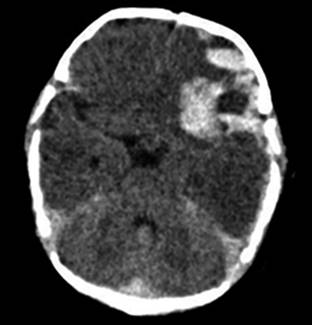

Seis horas después del ingreso presentó hipertonicidad generalizada y pérdida del estado de alerta durante un minuto. Posteriormente la paciente se encontraba somnolienta, pero con signos de hipertensión endocraneal (fontanela anterior abombada, bradicardia, hipertensión arterial) y falla ventilatoria, por lo que se inició ventilación mecánica y medidas para contrarrestar edema cerebral, llegando al coma inducido. Los hallazgos de tomografía de cráneo simple fueron: línea media conservada, sangrado intraparenquimatoso frontoparietal izquierdo, hemorragia subaracnoidea y en fosa posterior, así como isquemia hemisférica (Figura 1).

Se diagnosticó enfermedad hemorrágica tardía del RN, por lo que se inició vitamina K cada ocho horas y transfusión de plasma fresco congelado. El TP de control fue de 50 segundos y el TTP de 71 segundos, por lo cual se administró complejo protrombínico (carga 120 UI/kg y 80 UI/kg/6 horas). En virtud de los hallazgos tomográficos, se realizó craniectomía de urgencia, con drenaje de los hematomas subdural laminar y frontal, e intracerebral. Fue trasladada a la Unidad de Cuidados Intensivos con soporte ventilatorio invasivo y vasopresor (adrenalina a 0.15 μg/kg/min).